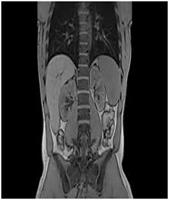

MRI of the Abdomen

Your doctor has ordered a MRI (Magnetic Resonance Imaging) of your abdomen. MRI uses a magnetic field, radio waves, and a computer to create images soft tissues, bones, and internal body structures. MRI of the abdomen allows physicians to examine the abdominal anatomy to rule out any structural abnormalities.